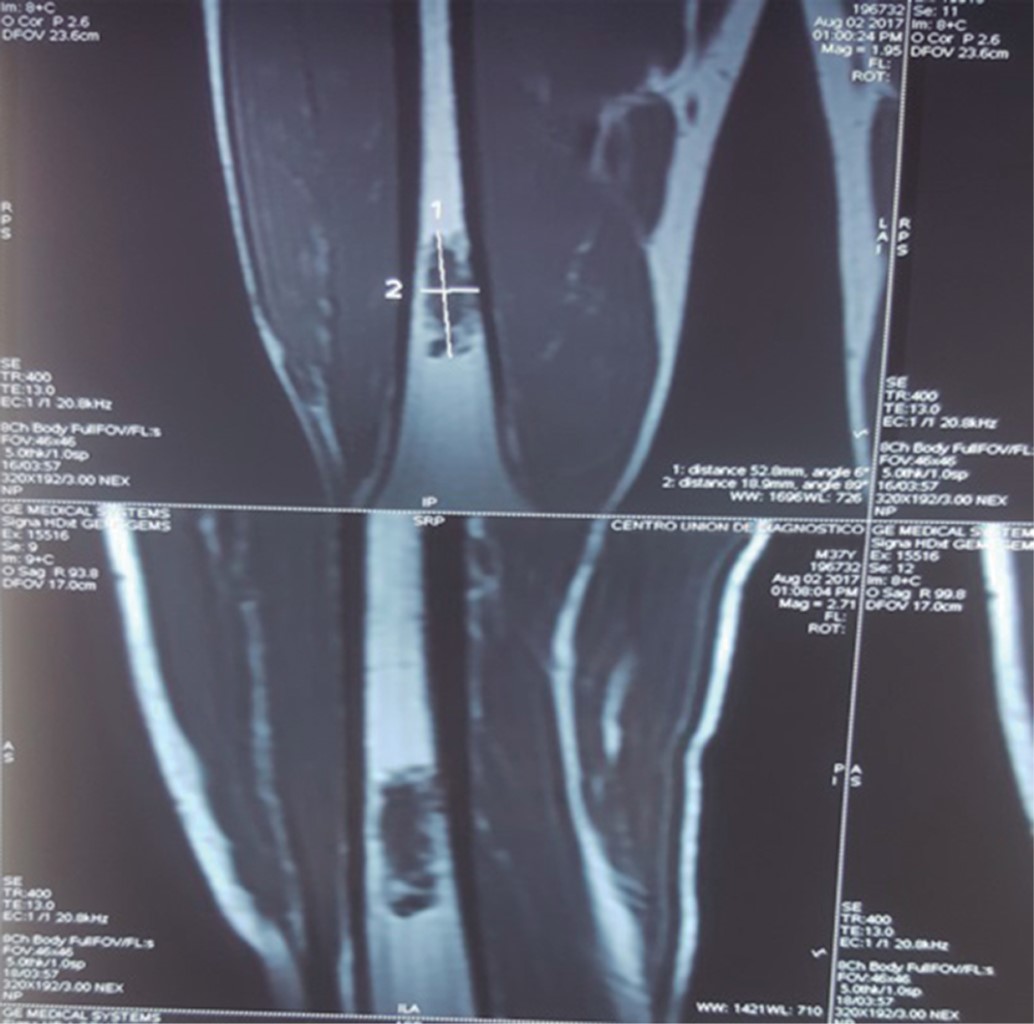

Femoral bone reconstruction after tumor resection, a case report and literature review

Chondrosarcoma are malignant tumors constituted by cartilaginous tissues, the second most common type after osteosarcoma among musculoskeletal tumors, as a general rule they are not sensitive to chemotherapy nor radiotherapy, therefore the treatment involves wide surgical resection with limb salvage, resulting in a bone defect that needs to be reconstructed. reconstruction options available range from endoprostheses, adjuvants after curettage or biological reconstruction using autograft or allograft. Here is a clinical case report of a male patient with massive femoral bone loss, following the resection of a central chondrosarcoma; the bone reconstruction was performed using segmental bone allograft and autograft in combination with platelet rich plasma (PRP), bone marrow aspirate (BMA) and Gelfoam, the reconstruction was stabilized with osteosynthesis material, specifically a locked compression plate (LCP). Strict follow-up was conducted until graft consolidation and integration, which occurred 12 months after the latest surgery. This technique is based on adherence to the principles of the recently introduced "diamond concept", which provides guidelines for the best possible intervention thus increasing the success rate of reconstruction and consolidation. With these strategies, a definitive treatment for bone loss is offered, which is technically accessible for orthopaedic surgeons, reproductible and cost-effective for the patient.

Figure 1